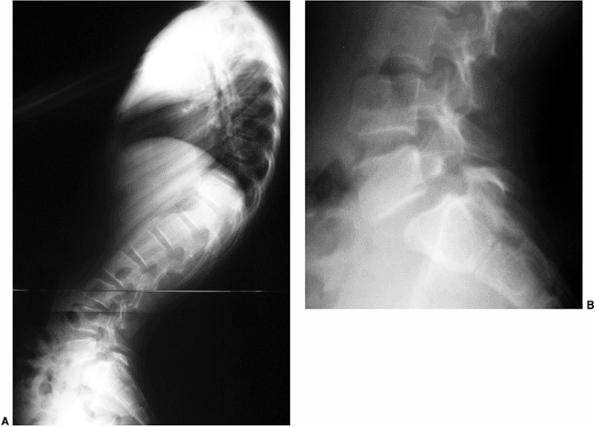

The suggested reason for the increased incidence of spondylolysis is

that increased stress is placed on the pars interarticularis because of

the associated compensatory hyperlordosis of

the

lumbar spine in Scheuermann disease. This increased stress causes a

fatigue fracture at the pars interarticularis, resulting in

spondylolysis. Ogilvie and Sherman (111)

found a 50% incidence of spondylolysis in the 18 patients they

reviewed. Stoddard and Osborn reported a 54% incidence of spondylolysis

in their patients with Scheuermann kyphosis (112).

![]() |

|

Figure 20.14 A and B: Lateral radiographs demonstrating spondylolisthesis with kyphosis.